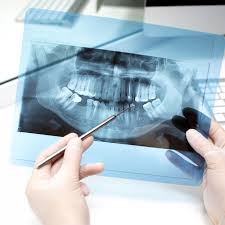

사랑니 발치 비용은 단순 발치인지, 잇몸을 절개해야 하는 난이도 높은 발치인지에 따라 달라집니다. 또한 치과의 위치(일반 치과, 대학병원, 전문 병원)와 보험 적용 여부에 따라서도 차이가 큽니다.